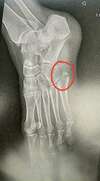

- Stade 2 : Rupture ligamentaire. Cette rupture survient lors d’une torsion importante de la cheville. Une immobilisation est préconisée, il peut être nécessaire d’aller faire une radio afin de vérifier qu’aucun os ne soit cassé. Ce stade d’entorse peut prendre environ 4 semaines à cicatriser.

- Stade 3 : Rupture ligamentaire + fracture ou arrachement osseux. Ce stade survient après une grosse torsion de la cheville. Une immobilisation par attelle ou par plâtre peut être envisagée, une radio doit être effectuée pour confirmer la fracture. La cicatrisation est d’environ 6 semaines.